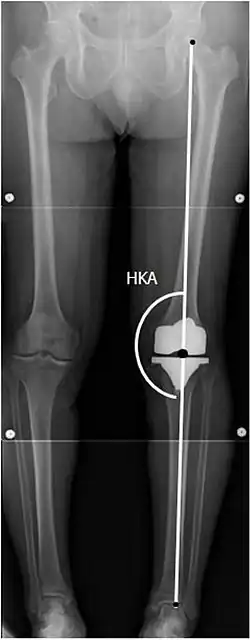

Knee replacement is routinely evaluated by X-ray, including the following measures:

![HKA: Hip-knee-ankle angle, which is ideally between 3° varum to 3° valgum from a right angle.[62]](./_assets_/X-ray_of_HKA_angle_with_knee_prosthesis.jpg)